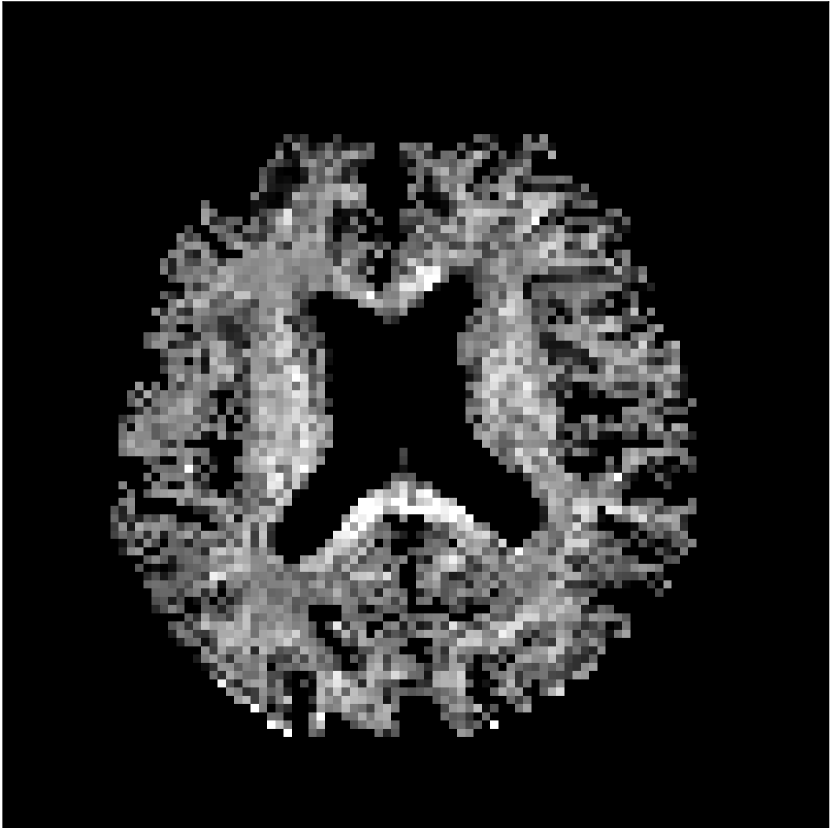

Figure 10 compares mean diffusivity maps across various partial Fourier factors between the CCNN and state-of-the-art methods.

No PF

7/8 PF

6/8 PF

5/8 PF

SoA

MD, μ𝜇\mum2/ms

CCNN

Figure 10: Comparison of mean diffusivity (MD) parameter maps across PF factors of 5/8ths, 6/8ths, 7/8ths, and without PF (No PF). The methods include state-of-the-art (SoA) and CCNN methods. Without partial Fourier, both methods are similar; however, as the PF factor increases, substantial artifacts are introduced in the SoA method, particularly around the lateral ventricles. The CCNN method is able to reduce the introduction of artifacts.

The methods perform similarly without partial Fourier acceleration, but as partial Fourier acceleration increases, the image is continually degraded in the SoA method, with "black voxels" appearing around the lateral ventricles. The CCNN method mitigates the appearance of these artifacts in the parameter maps.